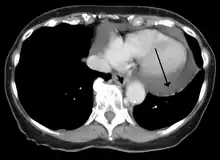

A CT scan image showing a pericardial effusion

Pericardial effusion due to malignancy. Note bulbous heart and primary lung cancer in right upper lobe.